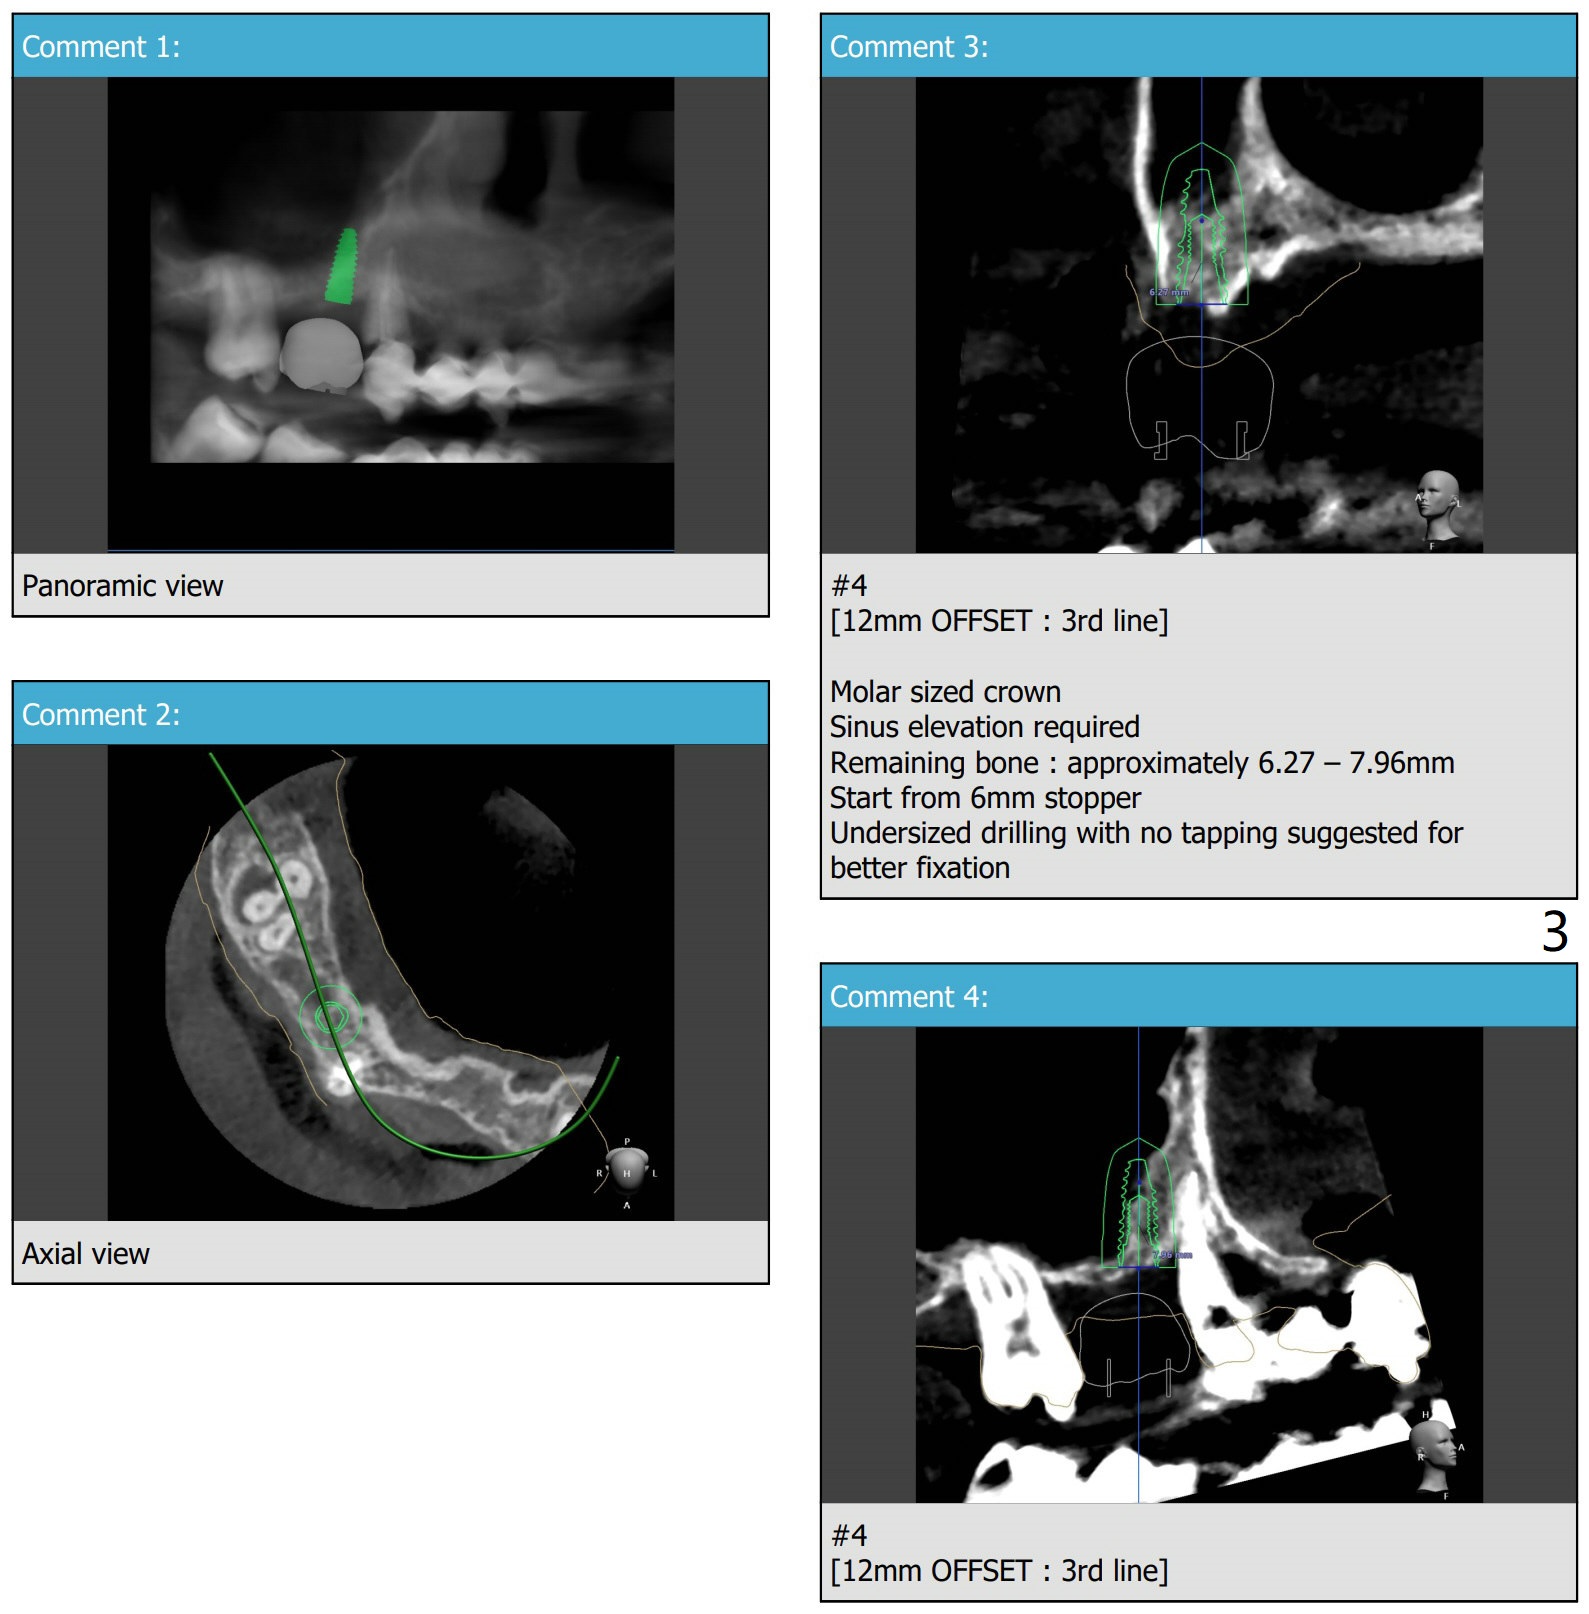

2个缺牙1个磨牙牙冠

植体可能需要包埋,至少6个月愈合。后来导板取消,徒手种植。